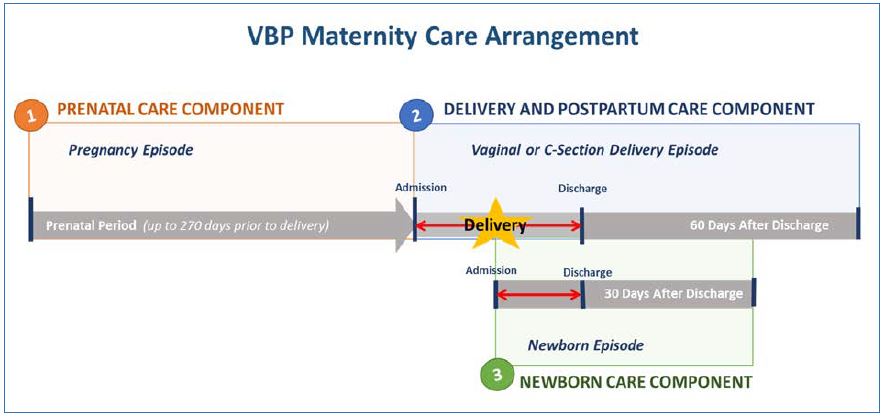

ectopic-pregnancy-unit-kk-, Maternity Care Value Based Payment Arrangement,

Maternity Care Value Based Payment Arrangement, 25 Weeks Pregnant Symptoms: Week 25 Of Pregnancy & Prenatal Care,